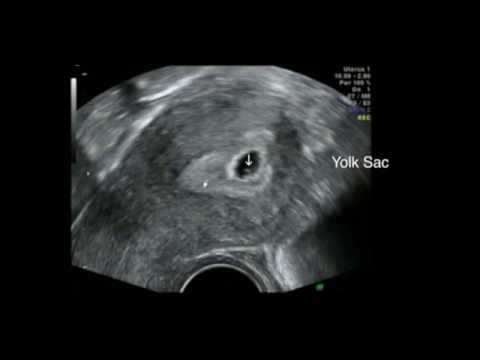

The purpose of the scan is to confirm viability, accurately establish gestational age, determine the number of viable fetuses, evaluate gross fetal anatomy and, if requested, assess the NT as part of the risk assessment for aneuploidy . Indications for early pregnancy scans (less than 12 weeks) Indications include:

An early pregnancy dating scan , when compared with scans later in pregnancy, can be more accurate when assessing the expected date of delivery . With maturity, the size of the baby correlates less to its age than in the early weeks . Why would I need a 7 weeks pregnant scan ? To see if one or more babies are present and assess gestational age .

Pregnant women should be offered an early ultrasound scan between 10 + 0 and 13 + 6 weeks to establish accurate gestational age . (Grade A recommendation) Ultrasound assessment of embryonic/fetal age ( dating ) uses the following assumptions: